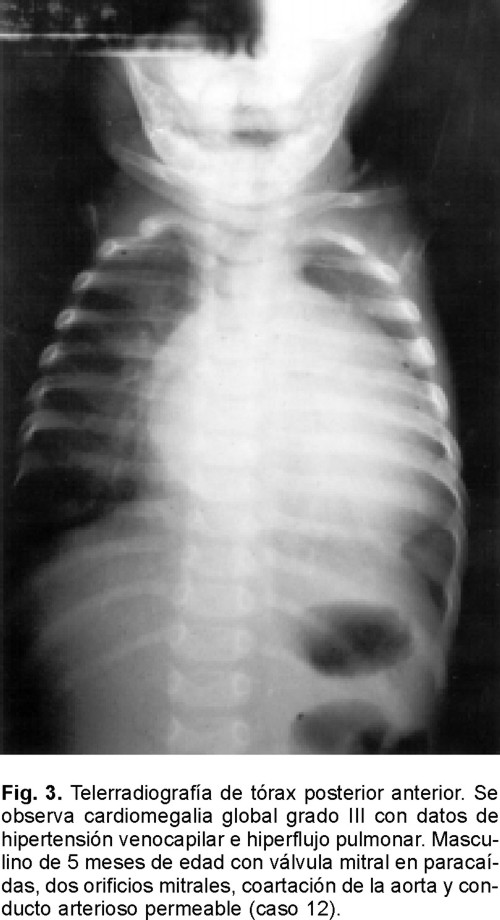

La telerradiografía de tórax mostró cardiomegalia III con datos de hipertensión venocapilar combinados con flujo pulmonar aumentado en 11 enfermos (68%), todos ellos tenían un cortocircuito de izquierda a derecha; dos enfermos (12.5%) con cardiomegalia III y datos de hipertensión venocapilar (Fig. 3), en un enfermo cardiomegalia III con flujo disminuido y cardiomegalia I en dos.